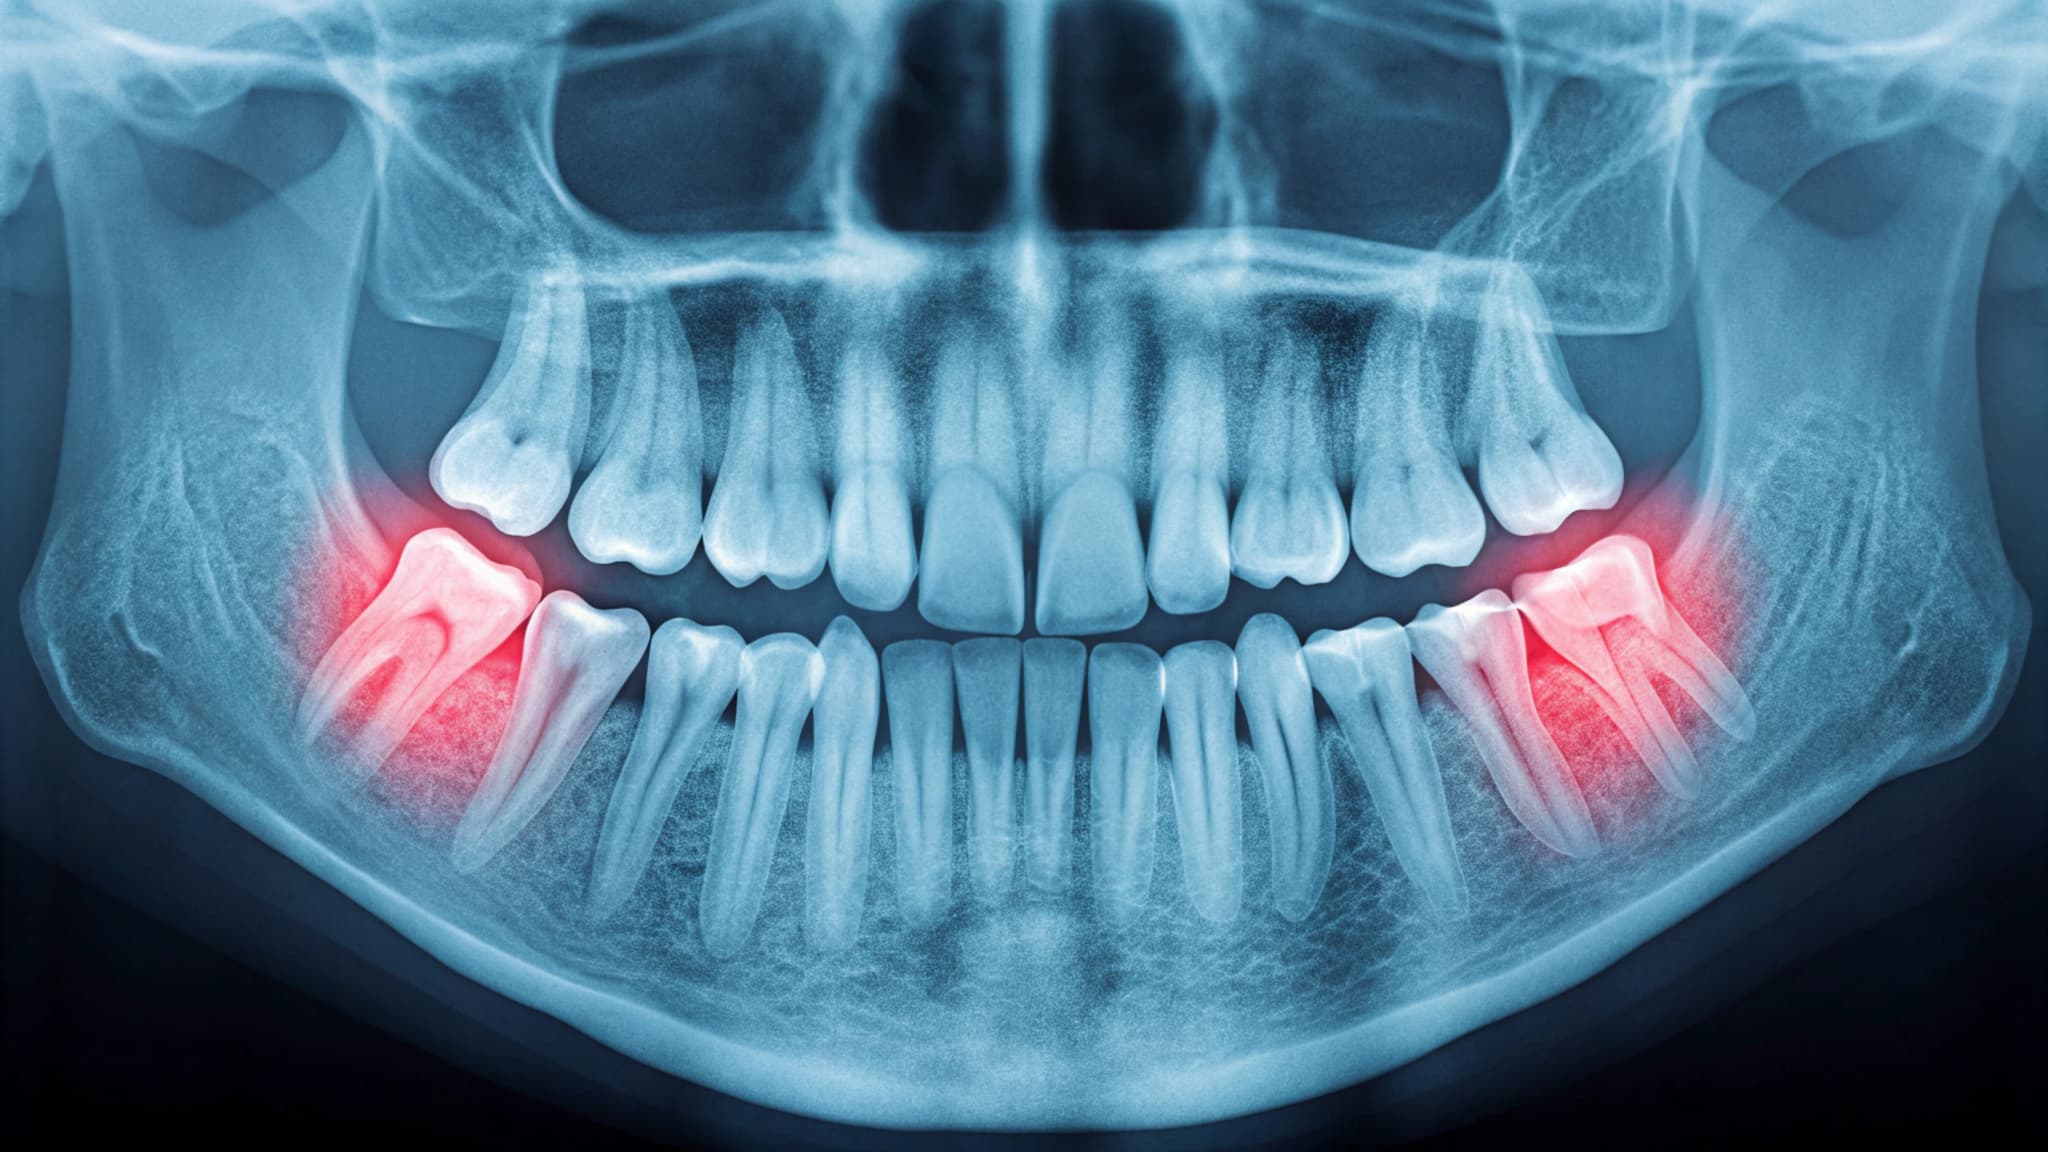

親知らずは、正式には第三大臼歯と呼ばれる奥歯で、上下左右の一番奥にそれぞれ1本ずつ、合計4本生える可能性がある歯です。多くの場合、10代後半から20代前半にかけて生えてきます。

その結果、親知らずが斜めや横向きに生えてくることがあり、歯ぐきの中に埋まったまま一部だけが見えている半埋伏(はんまいふく)の状態になるケースも多く見られます。このような生え方は、歯磨きが行き届きにくくなり、虫歯や歯肉の炎症の原因となることがあります。

親知らずの生え方

例えば、斜めや横向きに生えていたり、歯ぐきの中に一部だけ埋まっていたりする状態では、歯ぐきに圧力がかかり、炎症が起きやすくなります。また、歯がほかの歯や骨にぶつかっていることで、違和感や痛みを引き起こすこともあります。